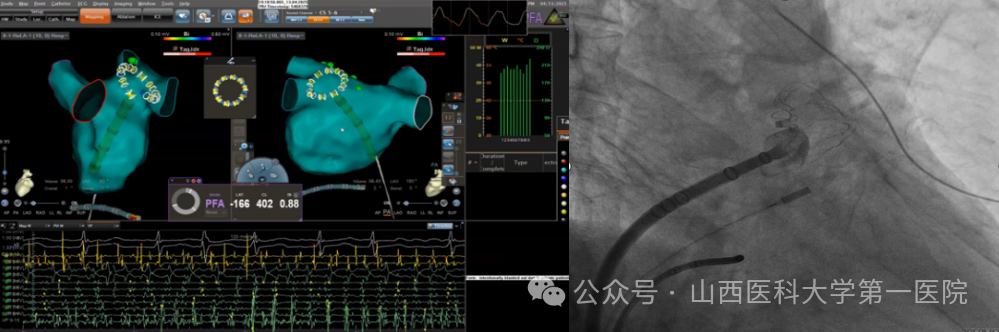

5月19日,山西医科大学第一医院电生理团队完成全国首批、山西省首例VARIPULSE脉冲消融导管指导下的房颤消融手术。该技术通过三维电生理标测系统(CARTO 3)与脉冲电场消融(PFA)的深度整合,实现了纯绿色房颤治疗的精准定位与安全消融,标志着房颤治疗迈入“三维可视化脉冲消融”时代,此次手术开展进一步丰富了该院在脉冲消融领域的临床经验,体现了对创新引领的不懈追求以及在房颤治疗领域的领先地位,更将让广大房颤患者受益于全球领先的医疗技术和服务,为他们的生活质量带来改善。

后续,电生理团队与麻醉科合作陆续开展了多例房颤脉冲消融术,均取得良好效果。心律失常亚专业王睿主任医师介绍:传统消融技术,如射频和低温,依赖于极端温度,这些温度本身会导致对组织的破坏;相比之下,非热能源的PFA技术在消融过程中具有组织选择性,能够减少热消融技术带来的风险。脉冲电场消融(PFA)具有细胞特异性——其靶向作用的心肌细胞对PFA更敏感,而平滑肌(如食管)和神经轴突(如膈神经)则更具耐受性。另外,脉冲消融能够避免食道损伤、肺静脉狭窄等传统消融并发症的出现,使手术安全性得到很大提高。结合电生理团队在零射线消融方面的经验,充分发挥三维脉冲消融优势,可精准显示导管位置与心脏组织的贴靠,量化消融标记消融灶,显著提高脉冲消融的成功率,同时可以脱离射线,减少医患辐射风险,提高手术安全性,缩短手术时间,该术式在临床的常规应用在使医院电生理诊疗水平再次走在全省甚至全国前例。